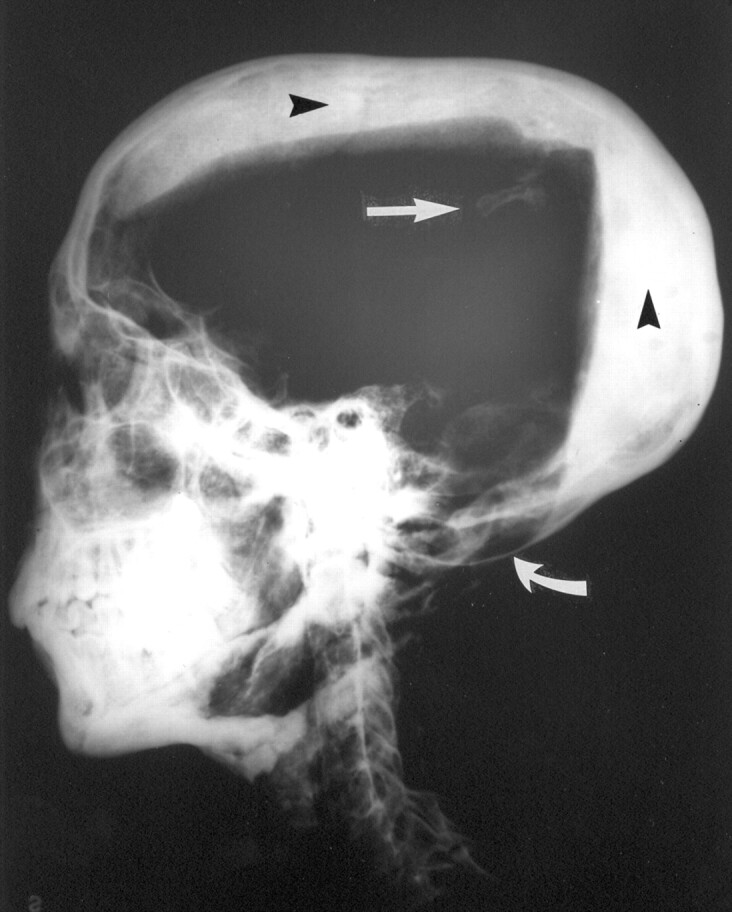

Fig 1.

Lateral view radiograph of Tutankhamen’s skull and cervical spine. Note the opaque layers of resin in the occipital and vertex regions (arrowheads), the bone fragments (straight arrow) that were probably dislodged during the 1925 autopsy, and the physiological thinning of the floor of the posterior fossa (curved arrow). (Reprinted courtesy of the University of Liverpool.)

The cranial-facial proportion appeared appropriate for a young adult male. The calvaria appeared to be intact. No skull fracture was identified. However, as discussed by Harrison (2, 4), two fluid levels were present, which resulted from the resin introduced at the time of embalming. The resin deposits in the vertex and occipital regions of the cranial vault were well seen on the lateral view radiograph (Fig 1). The resin in the vertex was seen on the frontal view radiograph (Fig 2). The sub-mental vertex view showed the resin in the occipital region (Fig 3). The presence of this hardened, opaque resin was actually helpful in understanding and refuting the commonly held theories of skull fracture and subdural hematoma.

No calcified membrane was seen in the posterior fossa. Two parallel linear opacities in the posterior fossa represented the lateral aspects of the floor of the posterior fossa on which rested the cerebellar hemispheres. Mild tilt of the head on the lateral view radiographs projected the contour of the floor of one side of the posterior fossa above that of the other. A lateral view radiograph of a skull phantom (Fig 5) showed that the parallel lines of the right and left sides of the floor of the posterior fossa project one cephalad to the other when the head was tilted. The appearance of the lateral view radiograph of the phantom was very similar to the appearance of the lateral view radiograph of Tutankhamen, confirming our impression that there was no calcified membrane, as suggested by Brier’s consultant (1), but only normal posterior fossa anatomy (except for the resin, as discussed above).

Posterior Fossa Bone Thinning

The other observation of Tutankhamen’s radiographs that has been used to impute a violent form of closed head trauma as the cause of his death relates to the occipital region on the lateral view radiograph. The reported thinning of the occipital bone can be easily understood by examination of the osseous floor of the posterior cranial fossa. The lateral aspects of the occipital bone expand and thin to accommodate the cerebellar hemispheres, which rest on them. Thinning of the occipital bone in this region is a normal finding. The reason that the thinning appears to be somewhat more pronounced on the lateral view radiograph of Tutankhamen is because the head is somewhat tilted laterally so that one lateral posterior fossa depression projects lower than the other. This tilt of the head also accounts for the horizontal attenuated line seen across the floor of the posterior fossa, thought by a consultant referred to by Brier (1) (who had only a photograph of the radiograph available rather than the actual radiograph) to be a calcified membrane. It is simply one side of the posterior fossa floor projecting above the other. Furthermore, if there were a calcified membrane in the posterior fossa at the time of death, the resin applied postmortem would not have crossed the margin of the membrane, which it obviously does on the lateral view radiograph. No calcified membrane was observed, and no evidence of a subdural hematoma was seen.